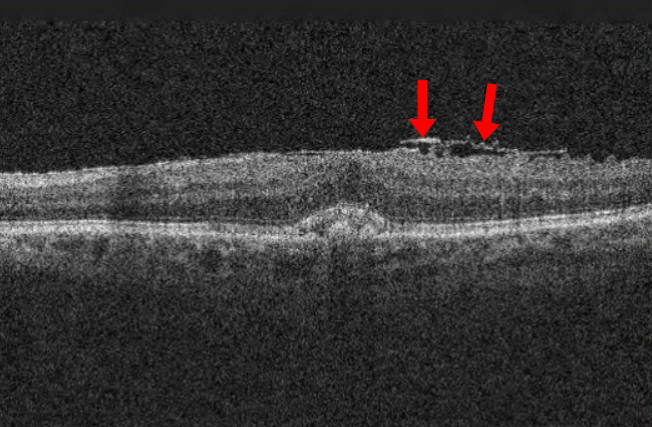

연세의대 안과 연구팀이 국제학술지 '망막'(Retina) 최근호에 발표한 논문에 따르면, 2017∼2020년 국민건강영양조사(KNHANES)에 참여한 1만5천240명을 분석한 결과 평일 평균 수면시간이 6시간 미만인 사람은 그렇지 않은 사람보다 망막전막 발생 위험이 25% 높은 연관성이 관찰됐다. 망막전막은 우리 눈에서 빛을 감지하고 뇌로 신호를 전달해 시력을 유지하는 핵심 부위인 망막의 앞 표면에 반투명한 막조직이 형성되면서 황반 기능에 이상을 일으키는 질환이다. 망막앞막, 황반주름 등으로도 불린다. 초기에는 뚜렷한 자각 증상이 없고 50세 이상 중장년층에서 발병률이 높아 노안으로 오인하기 쉽지만, 질환이 진행하면 물체가 휘어져 보이거나 상이 찌그러져 보이는 변시증, 시력 저하 등이 나타나고 결국에는 그 기능을 상실할 수도 있다. 연구팀은 이번 연구에서 망막전막 발생에 영향을 미치는 주요 변수로 나이(노화), 백내장 수술력, 이상지질혈증, 수면 부족 등을 꼽았다. 이 중에서도 수면 부족은 조절할 수 있는 위험 요인이라는 점에서 평소 일상생활에서 주의해야 한다는 게 연구팀의 분석이다. 연구팀은 수면 부족이 이어지면 망막 표면에서 활성화되는 여러 세포의 섬유화가 촉진됨으로써 결국 불필요한 막 조직이 만들어질 수 있는 위험이 커진다고 봤다. 실제로 만성적인 수면 부족은 전신의 염증 상태를 유발하고 면역 조절 기능을 약화하며, 혈관 항상성을 무너뜨려 심혈관질환이나 대사질환을 일으키는 것으로 알려져 있다. 여기에 노폐물을 제거하는 기능까지 떨어지면 유리체와 망막 사이 공간에 염증 매개물과 성장인자(TGF-β1)가 축적되고, 이에 따라 망막 세포들이 섬유화 반응을 일으킬 가능성이 높아진다는 게 연구팀의 설명이다. 이번 연구에서는 당뇨병 환자에게서 수면 부족과 망막전막의 연관성이 더 뚜렷했다. 당뇨병 자체가 미세혈관 염증과 망막 손상을 유발하는 만큼 수면 부족이라는 추가 요인이 더해지면 망막 환경이 더욱 취약해질 수 있다는 의미다. 망막전막은 진행 속도가 비교적 느려 일상생활에 큰 불편이 없으면 경과 관찰을 하기도 한다. 보통은 충혈과 통증 없이 시력의 변화만 나타나기 때문에 눈을 한 쪽씩 가리며 스스로 '암슬러 격자' 검사를 해봐야 한다. 이때 선이 휘어지거나 끊어져 보이는 등 시력 저하가 뚜렷하다면 안과에서 망막 검사, 빛간섭단층촬영 등을 통해 질환 여부를 확인하는 게 바람직하다. 만약 막이 심하게 달라붙어 망막 변형과 시력 저하가 심해지면 눈 속 유리체를 제거하고 섬유성 막을 직접 제거하는 유리체절제술이 필요하다. 다만 수술 후에도 변형된 망막 구조가 완전히 정상으로 회복되지 않는 경우가 많아 조기 발견과 예방이 무엇보다 중요하다. 김안과병원 망막병원 유영주 전문의는 "노년층의 망막전막은 발병률이 높지만, 초기에 자각할 수 있는 증상이 없거나 미미한 게 특징"이라며 "정기적인 안과 검진을 통해 본인의 눈 상태를 체크하고 적절하게 조치하는 게 노년기 눈 건강을 지키는 첫걸음"이라고 말했다.